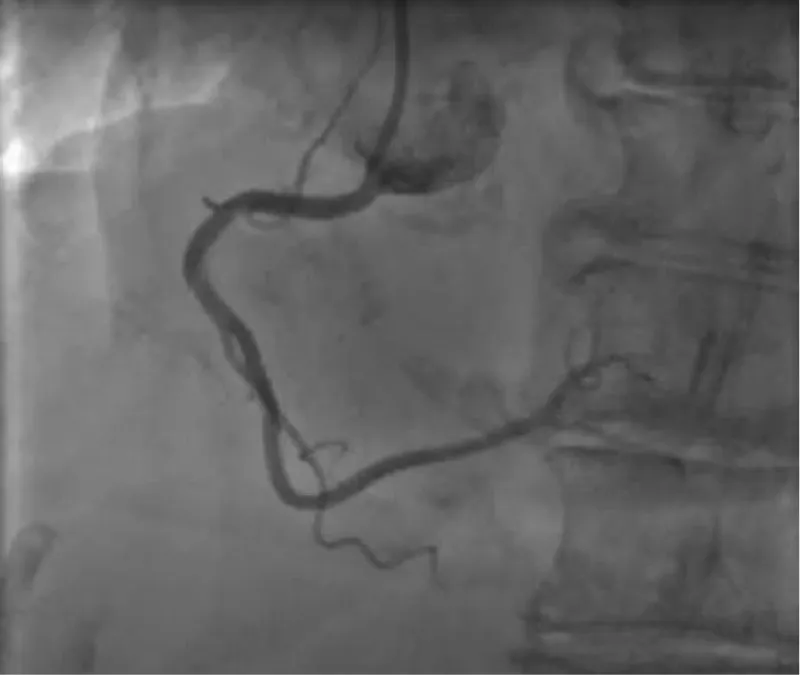

The clinical case concerns an 81-year-old woman with a history of systemic arterial hypertension, hypercholesterolemia, paroxysmal atrial fibrillation, chronic kidney disease, iron-deficiency anemia, and bilateral carotid atheromatosis for which she underwent a Carotid Endarterectomy (CEA) procedure. Additionally, she had a history of breast carcinoma, treated with surgery, subsequent chemotherapy, and ongoing Letrozole therapy. In 2019, the patient presented to the emergency department due to exertional dyspnea and low-threshold angina. During hospitalization, high average ventricular response (109 BPM) atrial fibrillation was diagnosed. Routine lab tests showed rising of hsTN-I (peak 800 pg/dL) and pro-BNP (peak 2476 pg/mL) and anemia Hb 9.1 g/dL. Echocardiography revealed severe depression of the left ventricular function (ejection fraction of 30%, with antero-apical akinesia) and low-flow-low-gradient aortic stenosis (mean gradient of 26 mmHg and AVAi of 0.5 cmq/m2 and SVi 29 mL/m2). So it was performed a Dobutamine stress Echo showed a rise of SVi up to 38 mL/m2 and a mean aortic gradient of up to 48 mmHg. Coronary angiography showed the right dominant coronary artery, of good caliber and course, with no angiographically significant lesions (Figure 1). The Left Main artery, with good caliber, had a 90% calcific stenosis at the distal segment, involving the proximal segment of the Left Anterior Descending artery. The Left Circumflex artery, with good caliber and course, presented a 30% ostial stenosis. The Intermediate Branch, with good caliber and course, showed 80% stenosis at the proximal segment (Figure 2). The Left Anterior Descending artery, also of good caliber and course, was diffusely atherosclerotic with a long, severely calcific 80% stenosis at the mid-distal segment (Figure 3). Therefore, the case was discussed by a multidisciplinary Heart team at our center. The STS score calculated indicated a mortality risk of 11.4%. Due to this high risk, surgical treatment was not considered, and the patient underwent a four-step percutaneous intervention. Before the intervention, a CT angiography was performed, revealing an aortic annulus area of 433.2 mm2, a perimeter of 75.3 mm, and a coronary height from the annulus of 10 mm. The right common femoral artery mean diameter was 6.1 mm2 and the external iliac artery was 8.4 mm2 with moderate tortuosity without significant calcification (Figure 4-6). Therefore, a 23 mm Edwards Sapien 3 valve was chosen. Our strategy consisted of 4 steps:

Figure 2: The Left Main artery, with good caliber, had a 90% calcific stenosis at the distal segment, involving the proximal segment of the Left Anterior Descending artery. The Left Circumflex artery, with good caliber and course, presented a 30% ostial stenosis. The Intermediate Branch, with good caliber and course, showed 80% stenosis at the proximal segment.